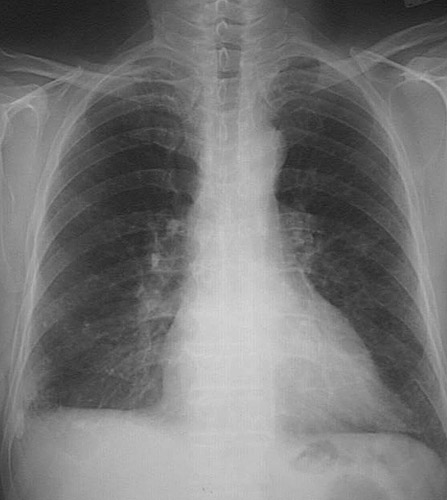

The chest radiograph seen here demonstrates increased interstitial markings with an irregular architecture, along with flattening of the diaphragmatic leaves, consistent with centrilobular emphysema.